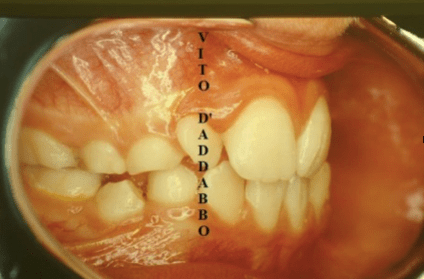

In una bocca che chiude correttamente i denti dell’arcata superiore sono collocati più esternamente rispetto ai corrispondenti dell’arcata inferiore. Nel morso inverso accade il contrario: in quello laterale sono i denti inferiori laterali a chiudere esternamente.

Questa malocclusione è il più delle volte dovuta a un mascellare piccolo, come nel caso riportato, dove manca anche lo spazio per l’incisivo laterale permanente di sinistra. I morsi incrociati vanno corretti precocemente perché possono provocare gravi asimmetrie del viso.

prima